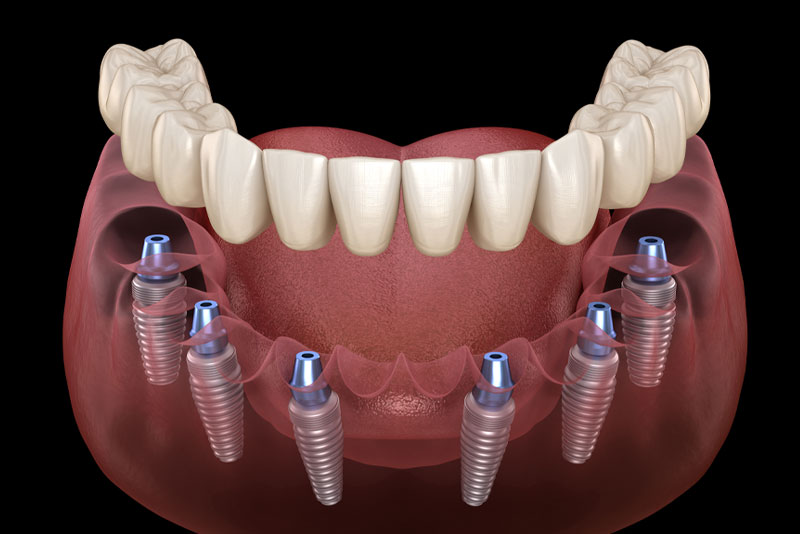

Is It Cost-Effective To Get Treated With Full Mouth Dental Implants In Woodbridge, VA?

Every investment people make on their oral health should give them a lasting return on it. But are full mouth dental implants in Woodbridge, VA, the most cost-effective treatment option for people to replace their missing teeth or traditional dentures with? Luckily, there are many reasons why full mouth dental implants are a cost-effective tooth […]

How Can Dental Implants Be Prevented From Failing In Woodbridge, VA?

Dental implants have a very low fail rate. In fact, the success rate of dental implants in Woodbridge, VA, is impressively high. However, dental implants can fail from time to time. In most of those cases, failure is preventable. When people go to a skilled periodontist for their dental implant treatment, they can rest assured […]